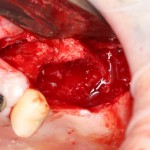

Имплантация и остеопластика: вместе или врозь? Часть II плюс Ankylos, плюс Geistlich